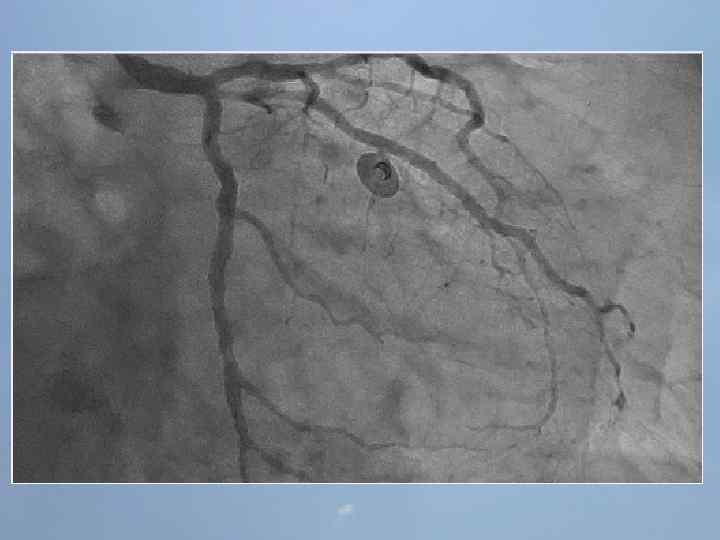

Пациент Б. , 54 года 29. 08. 13 около 10: 00, находясь на рабочем месте, почувствовал боль в груди. После 2 -ух приемов нитроспрея боль не уменьшилась, вызвал СМП. В 10: 20 первой бригадой СМП зафиксирован подъем ST на ЭКГ, начата ТЛТ, вызвана реанимационная бригада. В 10: 50 на месте вызова в присутствии реаниматолога у пациента развивается остановка кровообращения по типу фибрилляции желудочков. Выполнялась СЛР с непрямым массажем сердца, ИВЛ мехом, дефибрилляцией. В течение транспортировки фибрилляция рецидивировала еще 4 раза. Пациент доставлен в ООКБ в 11: 30, минуя приемное отделение госпитализирован в ОРИТ ОИМ.

Проведенные мероприятия: Обезболивание – морфин 1%-1 мл; Введена полная доза пуролазы – 6 млн МЕ; Дана нагрузочная доза клопидогрела - 300 мг; Начата в/в инфузия гепарина – 1000 МЕ/час; Дофамин 4% - в/в через ДЛВ; С противоаритмической целью: Кордарон 300 мг болюсом, затем 600 мг – капельно; Лидокаин 120 мг в/в; Магния сульфат 25% - 15 мл в/в; Калия хлорид 5% - 10 мл в/в.